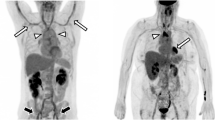

As PMR and GCA frequently overlap, typical FDG joint uptake patterns should be reported, including uptake in glenohumeral synovia, subacromial-subdeltoid bursa, supraspinatus tendinitis and biceps synovitis (shoulder), trochanteric/ischial bursa, hip synovia, interspinous regions of the cervical and lumbar vertebrae, or the synovial tissue of the knees if present, including the use of a standardized 0-to-3 grading system [74, 75] (Fig. 2).

FDG-PET. Low (grade 1), intermediate (grade 2), and high (grade 3) FDG uptake patterns of the large joint regions in PMR patients, including SUVmax of the shoulders. Ratio is defined as average SUVmax in the shoulders divided by the liver region. The total number and intensity of affected joints is the highest for the right-positioned patient